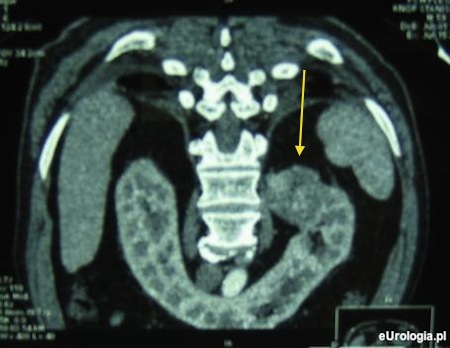

Fot. Guz nerki podkowiastej - obraz w badaniu tomografii komputerowej. Guz zaznaczono strzałką.